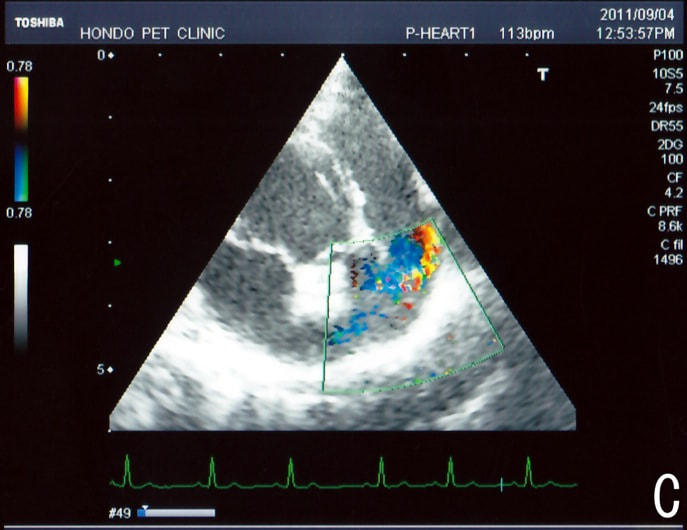

C:超音波画像 肺動脈領域の異常血流

D:左心系の拡張による二次的僧帽弁逆流

左側胸壁よりLevine 4/6の連続性心雑音が聴取された。胸部レントゲン検査において心拡大が認められ、超音波検査においても肺動脈領域に連続的な異常血流が観察された。大学病院を紹介受診され、手術が行われた。現在はACE阻害薬のみの内服で補助的治療を行っている。